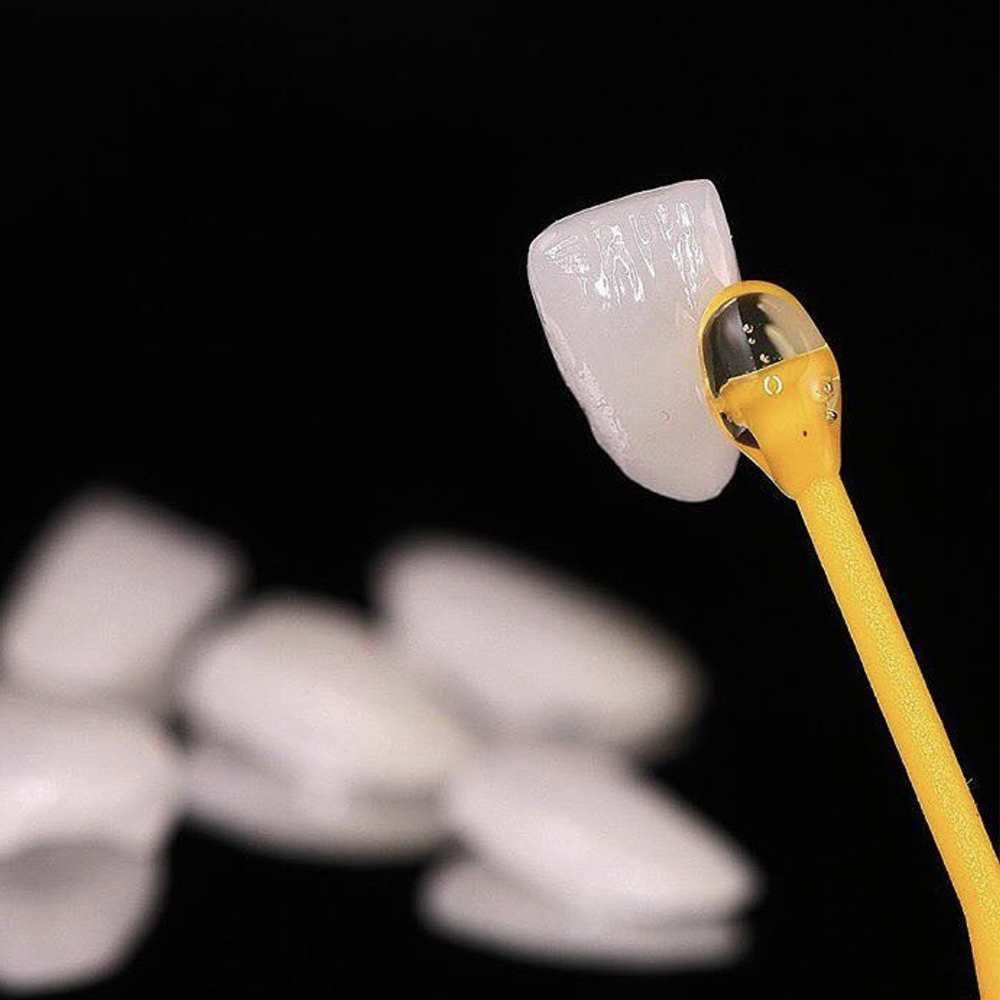

Le faccette dentali in ceramica sono restauri adesivi minimamente invasivi ad alta valenza estetica.

Grazie a preparazioni minimali limitate allo smalto dentario o addirittura senza toccare in alcun modo la superficie dei denti con restauri “addizionali” (tecnica “no-prep”), è possibile realizzare faccette di spessore medio pari a 0.5 mm.

La tecnica “no-prep” prevede la possibilità di applicare delle faccette senza limare in alcun modo i denti ma solo condizionandone le superfici con appositi adesivi. In linea con la cosiddetta “minimal intervention dentistry” (odontoiatria minimamente invasiva), tale approccio è estremamente conservativo, dal momento che non interferisce in alcun modo con la struttura e la resistenza dei denti.

La tecnica no-prep si abbina spesso alla realizzazione di restauri parziali chiamati “addizionali”: qualora non sia necessario ricoprire l’intera superficie di uno o più denti, è possibile fabbricare dei piccoli frammenti di ceramica che possano essere cementati laddove necessario, per riempire uno spazio o ripristinare, ad esempio, una cuspide fratturata.